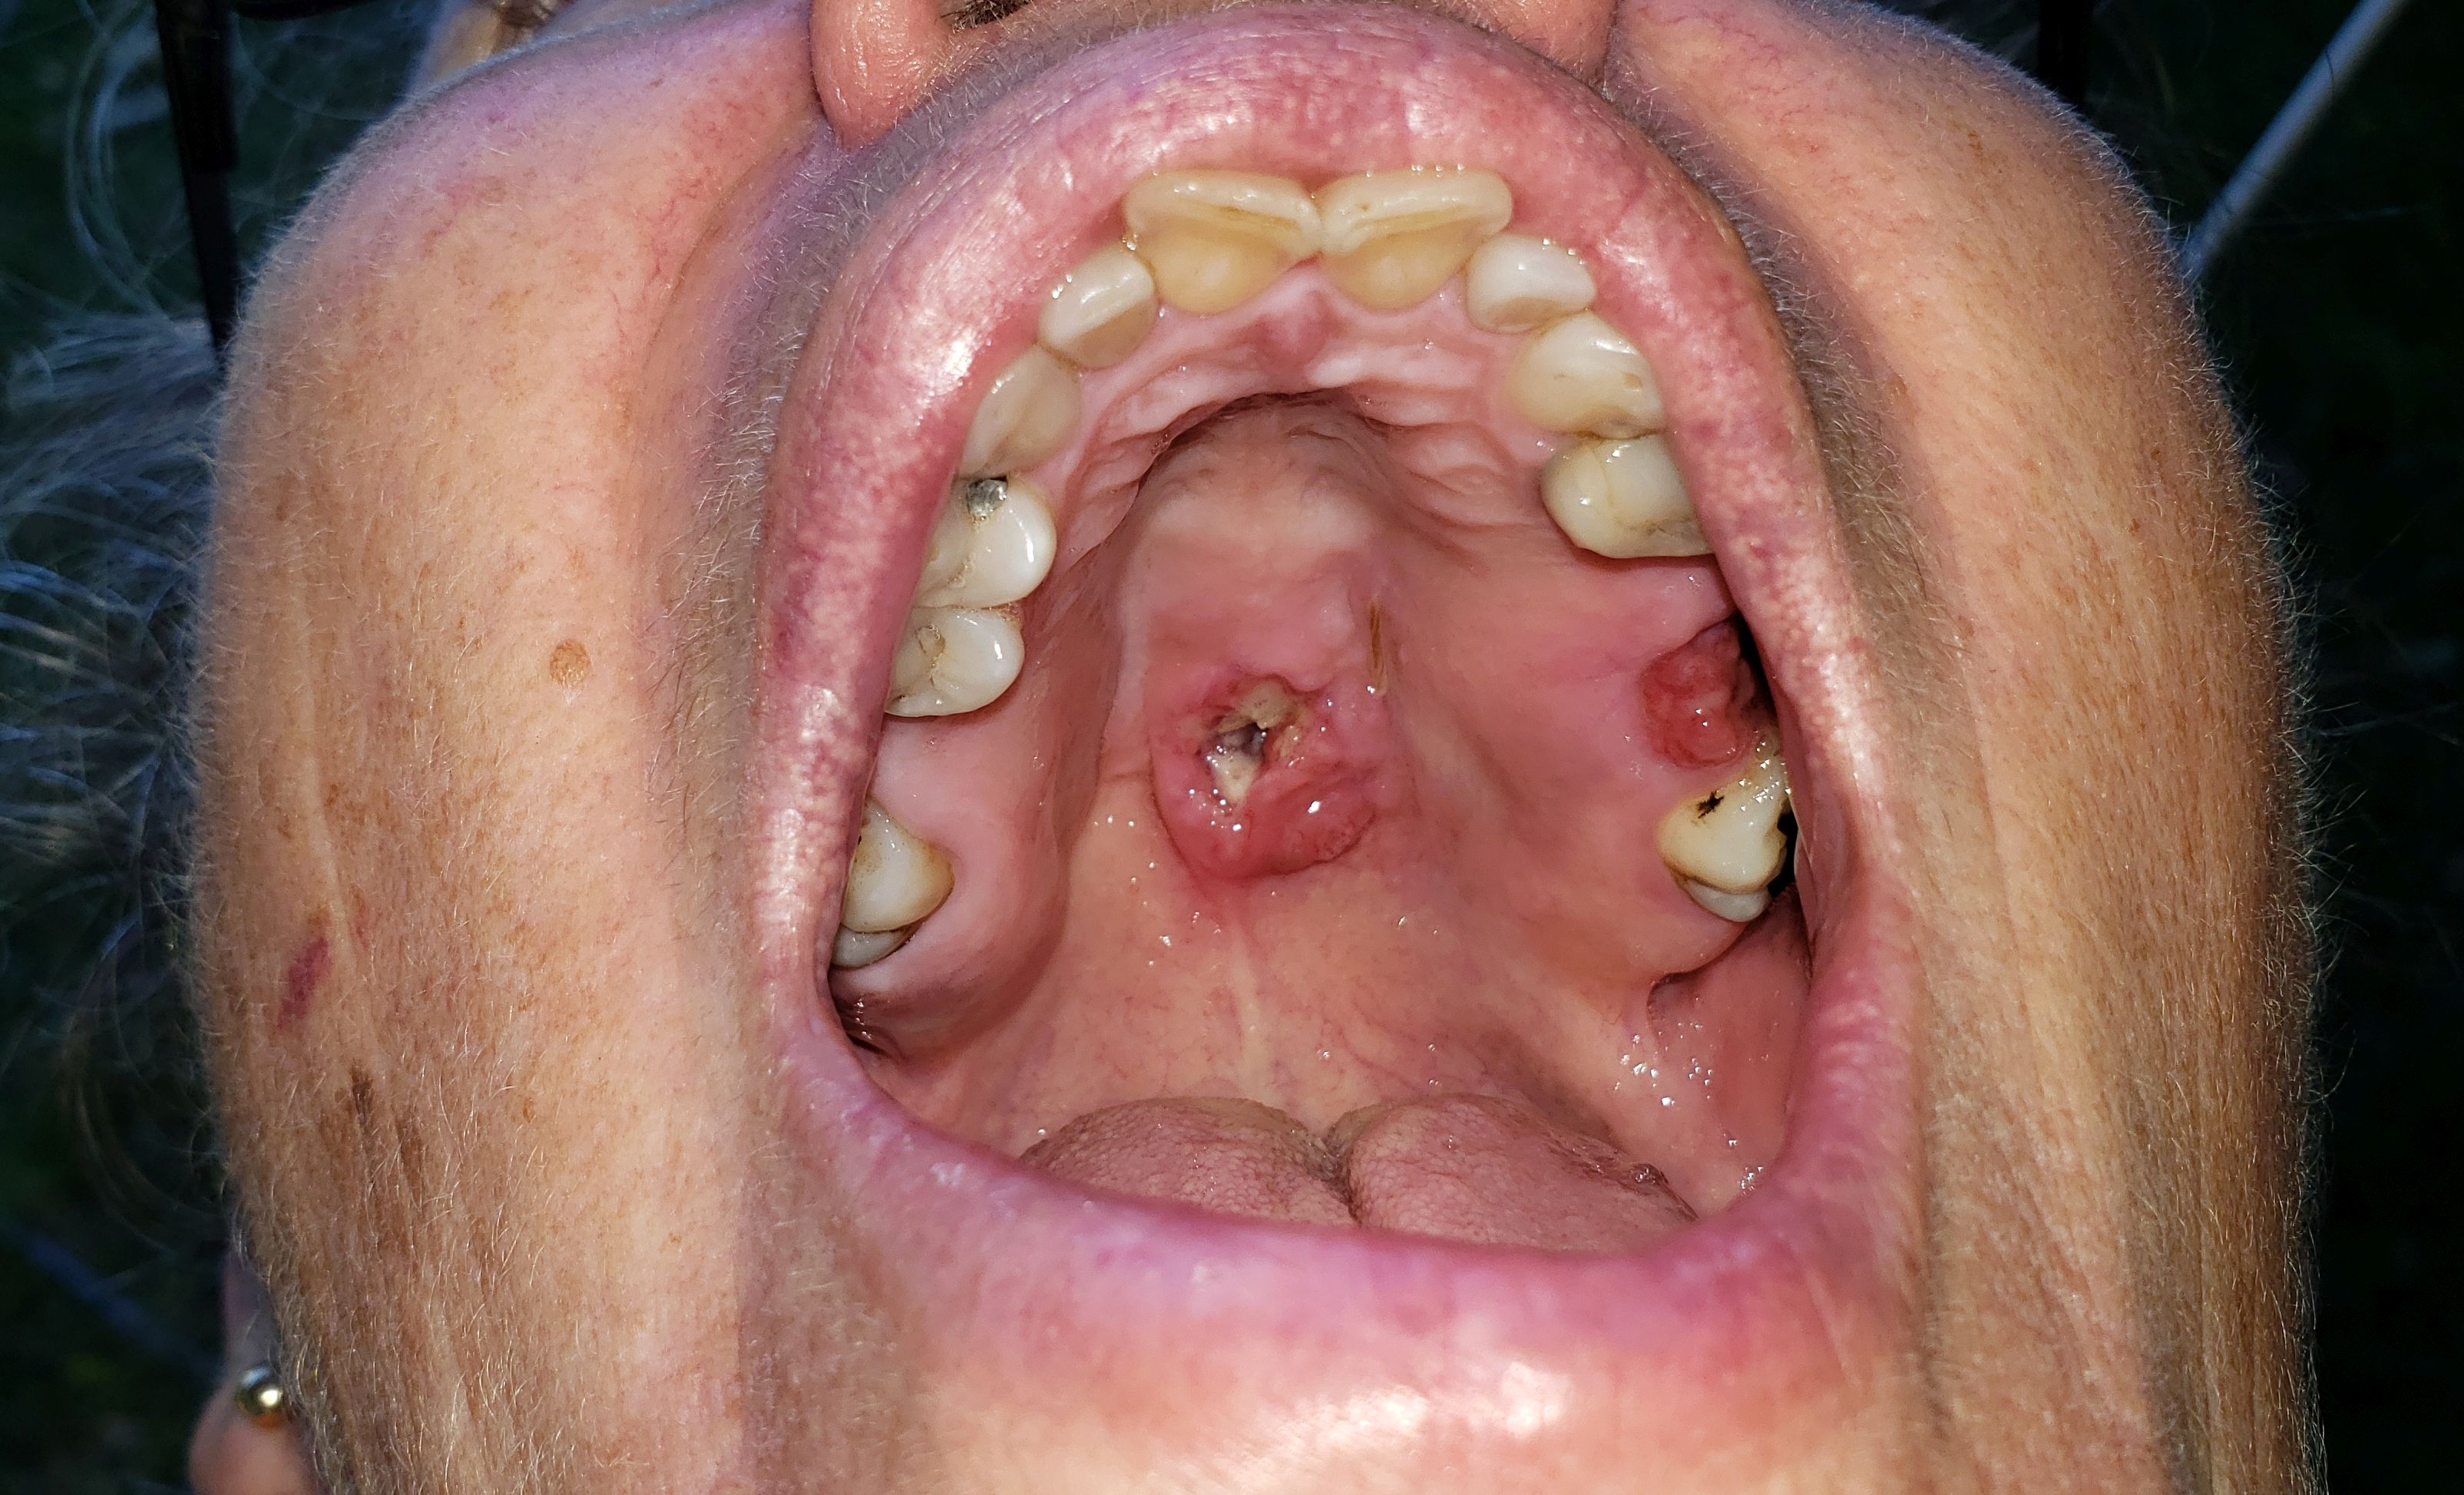

mouth cancer before biopsy and surgery 2019

27th October, 2019 the hole in my palette is getting rather large now.

Today while out shopping I noticed that a large piece of mucus or flem fell out of the hole in my palette, and went down the back of my throat causing me to gag and nearly be sick. My tongue went straight up to where the hole is and I could feel that there was now a large hole in the top of my palette.